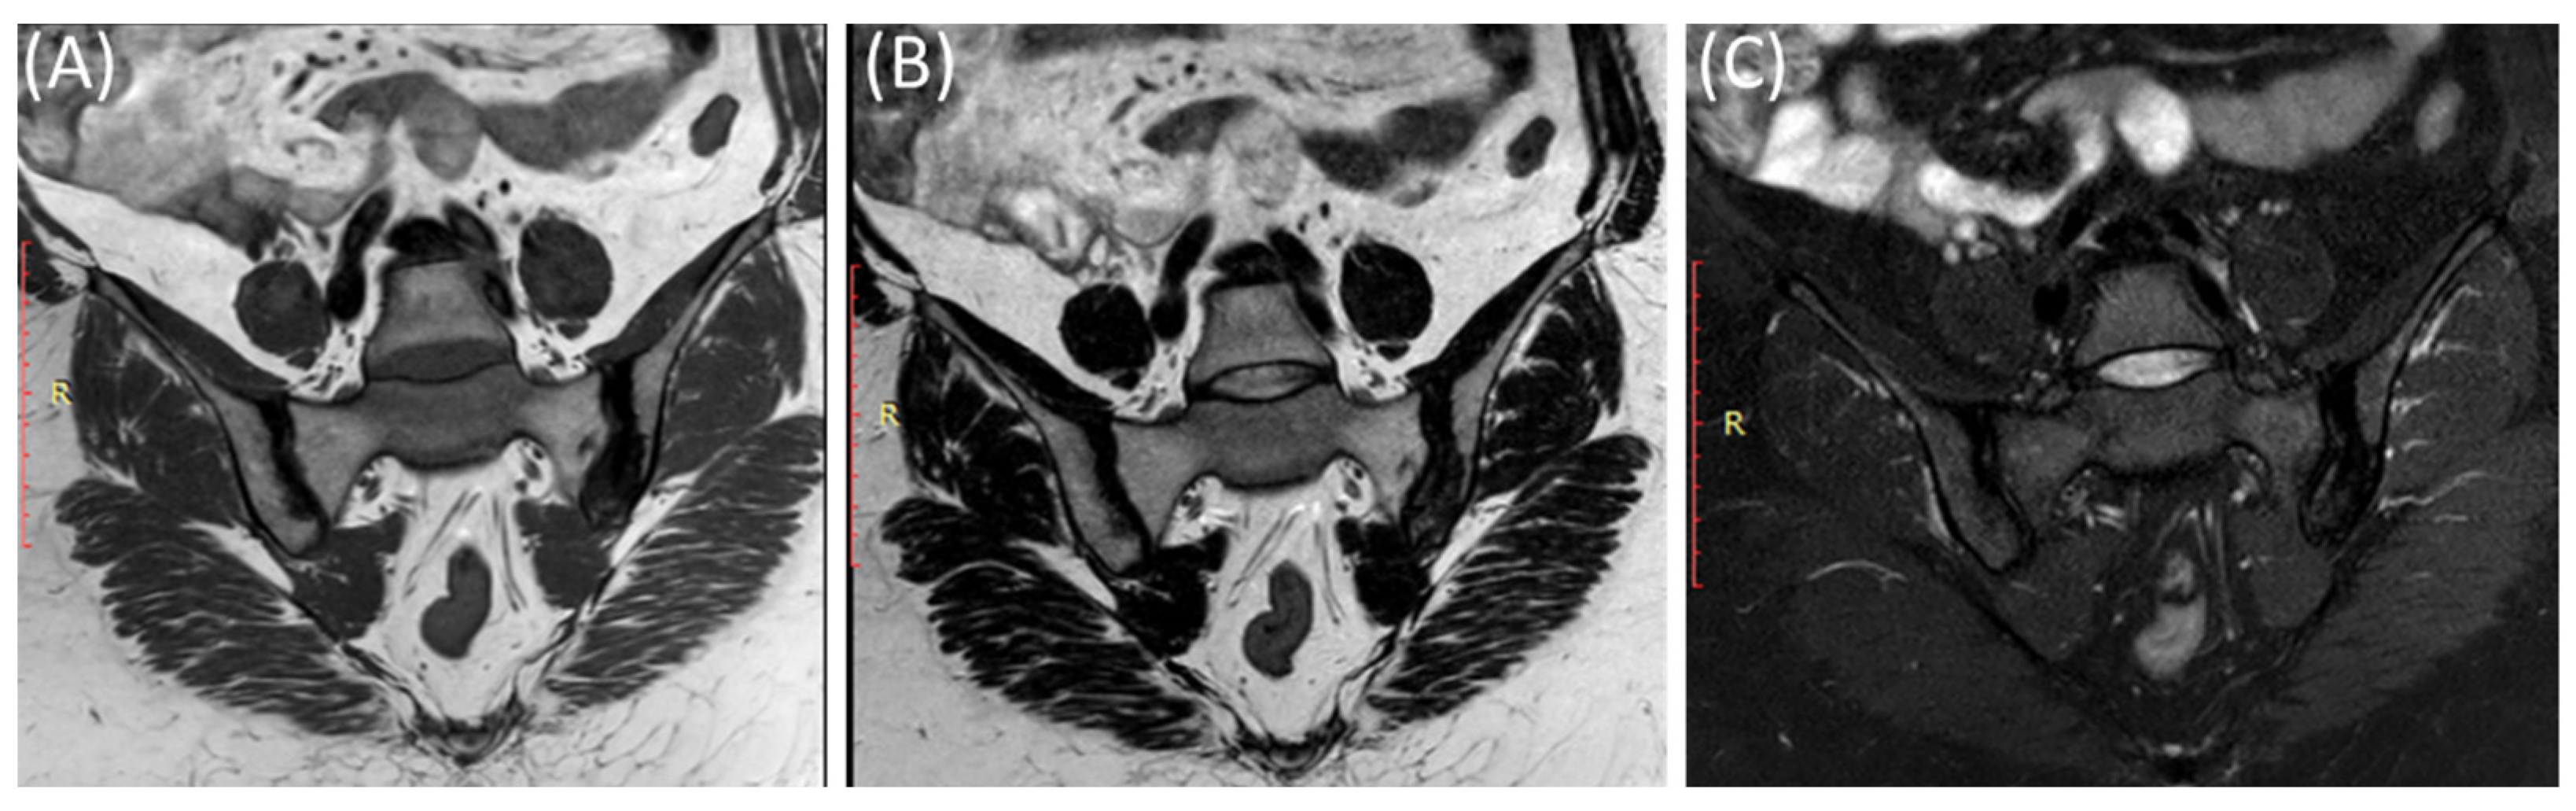

Figure 6.

Coronal T1-WI image (A), coronal T2-WI image (B) and coronal T2-fat suppression image (C) showing sclerosis and mild irregularity in both sacroiliac joints, more on the left side with no evident bone marrow edema in a 52-year-old female with chronic low back and hip pain suggestive of bilateral chronic sacroiliitis.